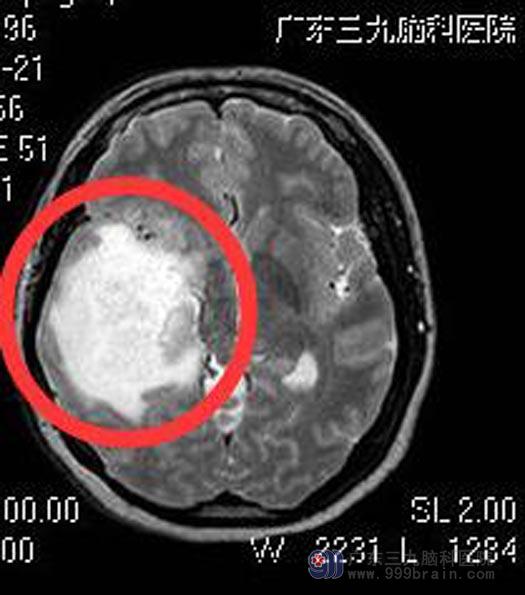

术前MR

岛叶是所有大脑脑叶中唯一隐藏在脑组织内部的高度发达的脑结构,被表面的额颞顶叶构成的岛盖和大脑中动脉主干和分支构成的血管墙所包绕。

岛叶胶质瘤属于脑深部的肿瘤,以低级别为主,由于不在大脑表面,而且有大脑中动脉及其分支走行其表面,手术难度非常大,因其解剖的特殊性,要想多切一些,就必须在血管缝隙里一点一点地把肿瘤掏出来。虽然可以使用包括唤醒麻醉、术中超声、神经导航,诱发电位和皮质电刺激等先进的辅助技术和技巧,岛叶胶质瘤的切除对于神经外科医师仍然是一个不小的考验。